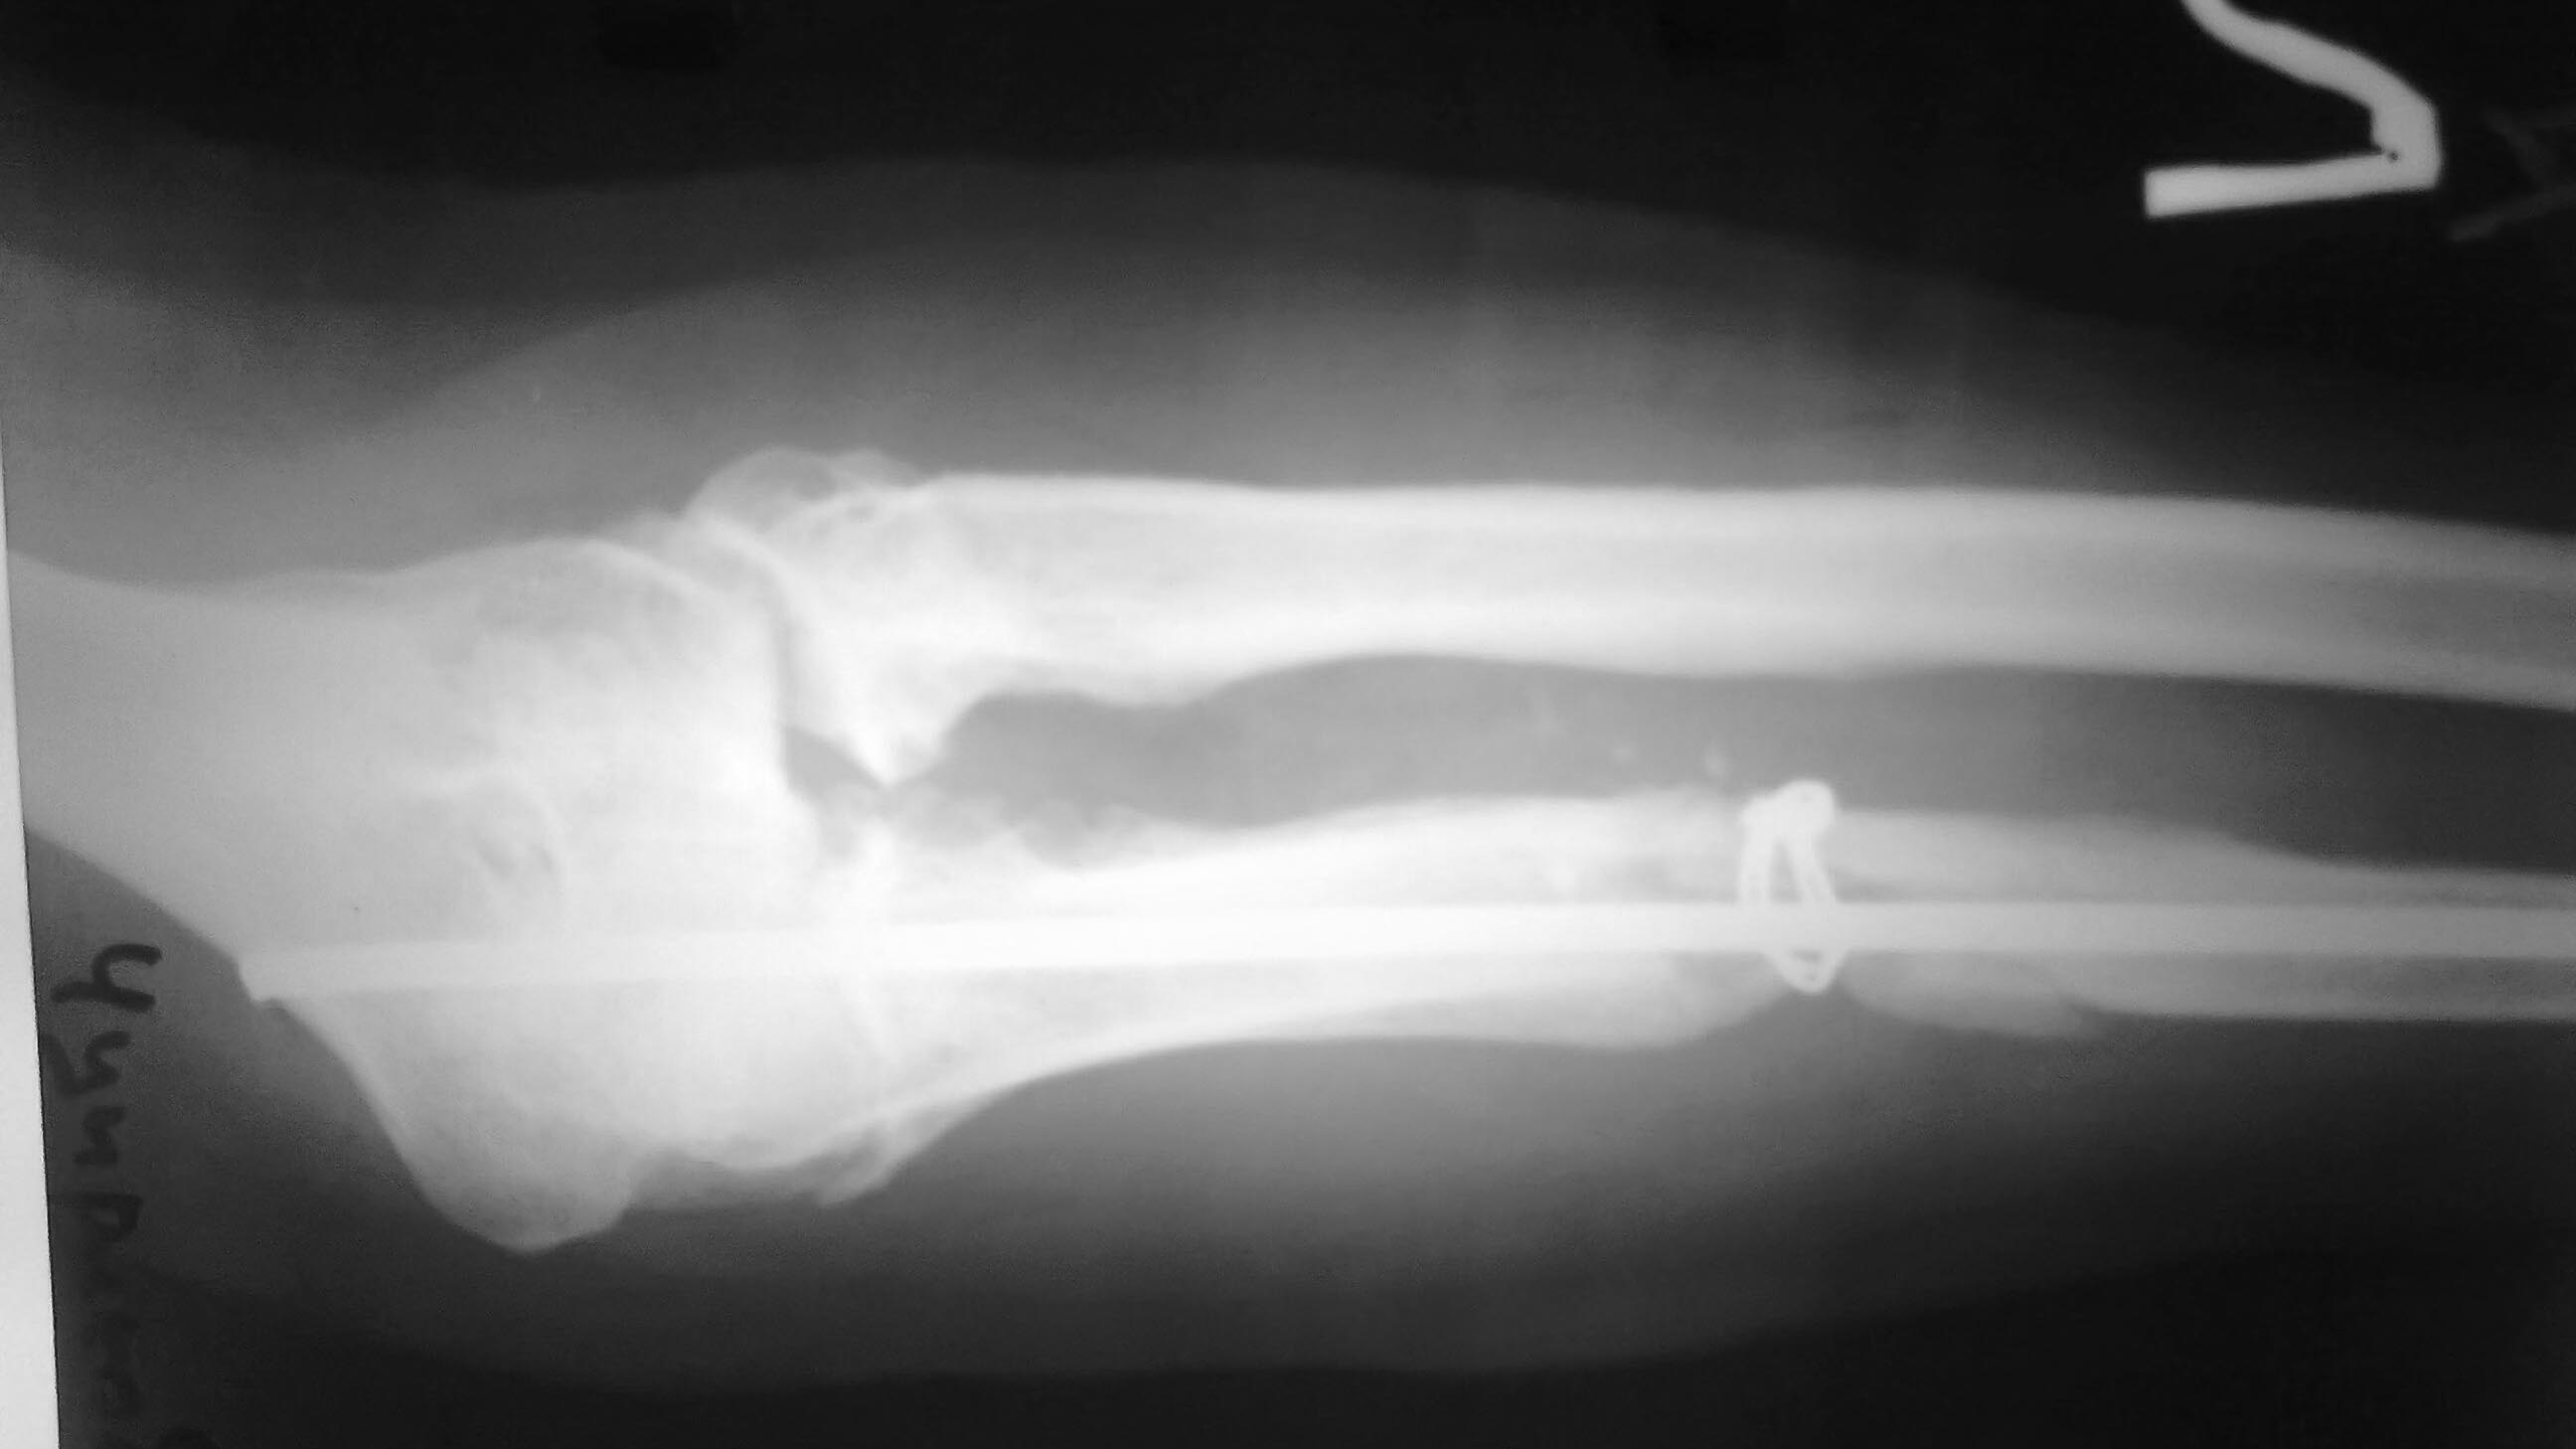

[Ortho] Ложный сустав локтевой кости.

Больной оперирован 7 мес назад МОС  локтевой кости гвоздем+непонятный

серкляжик.Перелом не сросся металоконструкции удалены и больной в

свободном поиске следуешего хирурга,да вот беда несколько стеснен в

средствах.Локоть с его слов  деформирован с юности(вывих головки лучевой

кости,но до травмы обьем движений с его слов был полный).Сейчас стоит

проблема выбора:1 вариант резекция головки и компрессия аппаратом

Илизарова 2.Резекция головки луча и БИОС с компрессией локтевой

кости3.Или  сделать остеотомию локтевой и заместить дефек и не трогать

головку луча.Подскажите оптимальный вариант.